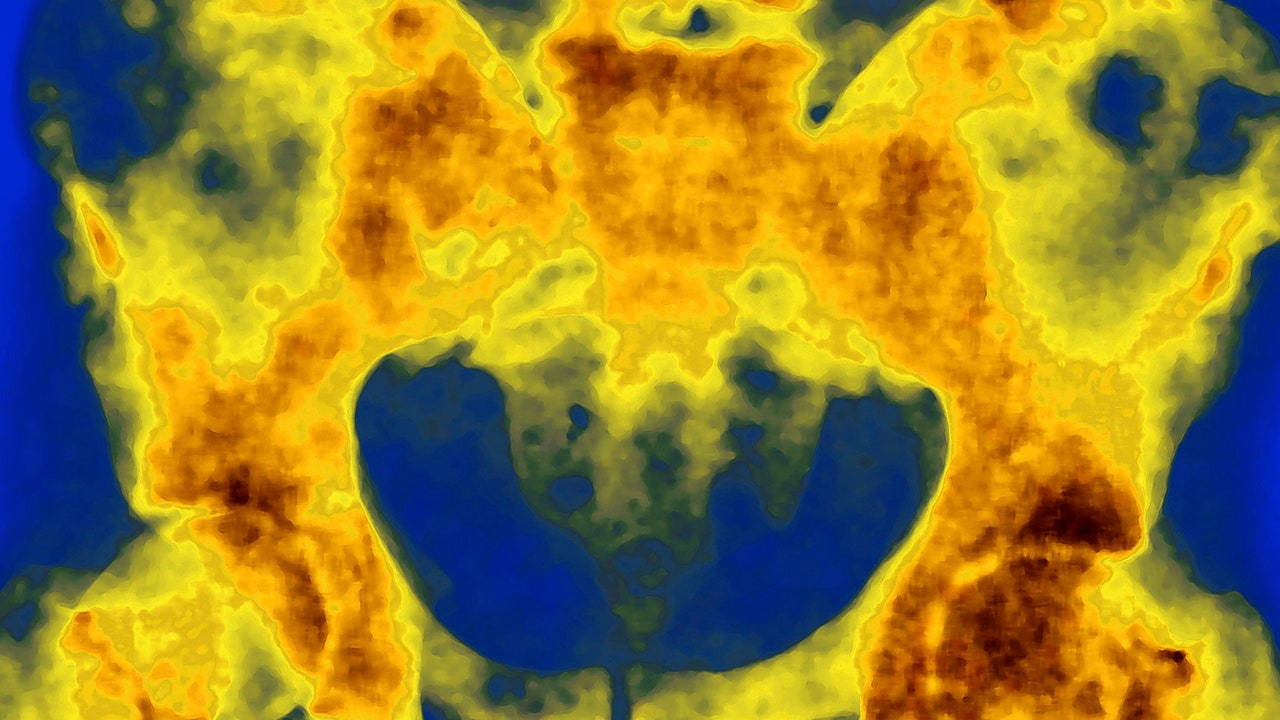

The study tested an emerging class of medicine called radiopharmaceuticals, drugs that deliver radiation directly to cancer cells. The drug in this case is a molecule that contains two parts: a tracker and a cancer-killing payload.

Trillions of these molecules hunt down cancer cells, latching onto protein receptors on the cell membrane. The payload emits radiation, which hits the tumor cells within its range.